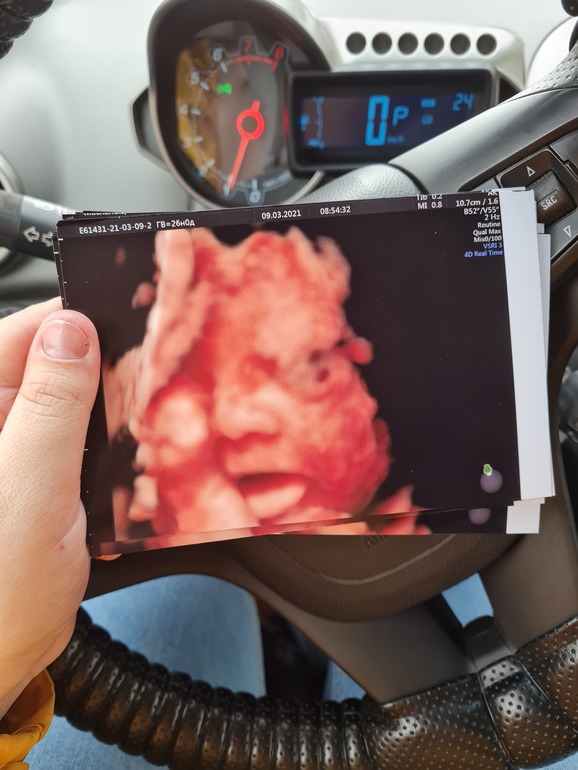

3Д УЗИ в 26 недель, фотопуз)

Вот такая красота получилась😋

Что-то жевала, бормотала, улыбалась и показывала свой маленький язычок)

По показателям все конфетно 👌🏻

Вод норма, плацента степень зрелости 1, органы без нареканий, кровотоки тоже, шейка абдоминально 36 точно, врач спрашивал смотреть ли вагинально, я отказалась, размер хороший, смысл раздеваться)

Вес сегодня(26 нед ровно) у крошки 945 гр , у Евы в 26 недель тоже ровно был вес 910 гр)